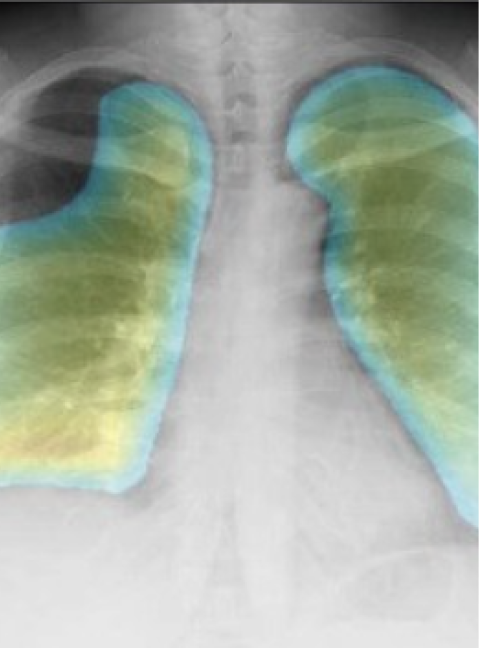

胸部CR×肺炎

DoctorNET JLK-CRP

胸部CR画像より、肺炎の確信度に応じたラベル・病変上のヒートマップを表示します

- 発熱外来での、肺炎の見落とし予防として

- 販売名

- 胸部X線肺炎検出エンジン DoctorNet JLK-CRP

- 医療機器承認番号

- 30300BZX00339000

- 一般的名称

- X線画像診断装置ワークステーション用プログラム

- クラス分類

- クラスII

- 承認年月日

- 令和3年12月9日

- 種別

- プログラム(01) 疾病診断用プログラム